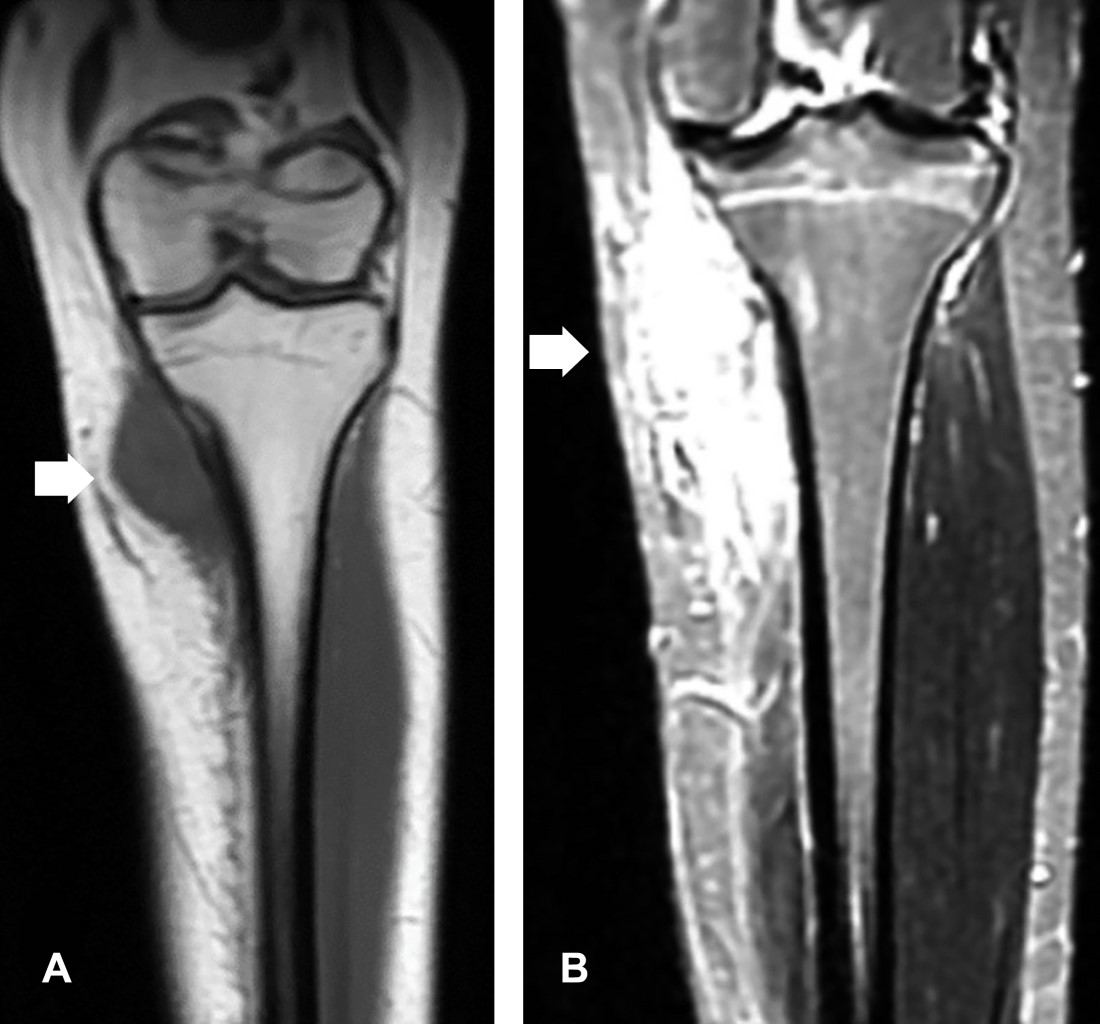

Mujer de 16 años, con crecimiento paulatino de masa en tercio superior de tibia izquierda con seis meses de evolución, no asociada a dolor ni limitación al movimiento. A la exploración masa palpable, no dolorosa, en área de bursa anserina, de consistencia dura, fija a planos profundos. La resonancia magnética (RM) (Figura 1) mostró: lesión en metáfisis de tibia izquierda, con intensidad de señal baja en T1, cortical indemne con discreto aumento de señal, sin afección medular, presentando intensidad alta en T2. La gammagrafía mostró señal en tibia izquierda, con sospecha clínica de osteosarcoma vs condrosarcoma, la biopsia transoperatoria reportó proliferación osteocondromatosa parostal (Figura 2), efectuando resección marginal, extracción de pseudocápsula y decorticación. Se dio de alta, con vigilancia cada dos meses.

Figura 1